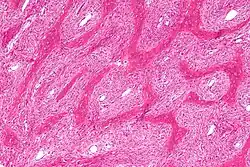

| Micrograph showing fibrous dysplasia with the characteristic thin, irregular bony trabeculae and fibrotic marrow space. H&E stain. | |

Fibrous dysplasia is a mosaic disease resulting from post-zygotic activating mutations of the GNAS locus at 20q13.2-q13.3, which codes for the α subunit of the Gs G protein-coupled receptor.[13] In bone, constitutive Gsα signaling results in impaired differentiation and proliferation of bone marrow stromal cells.[14] Proliferation of these cells causes replacement of normal bone and marrow with fibrous tissue. The bony trabeculae are abnormally thin and irregular (bony spicules on biopsy).